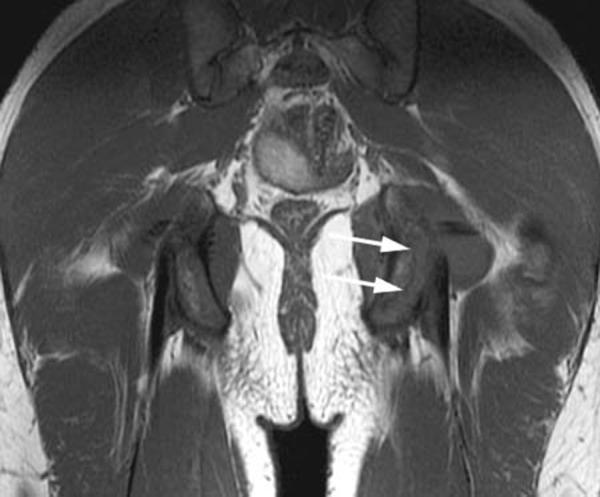

Apophyseal avulsion injuries of the hip and pelvis are frequent athletic injuries in children and adolescents, most commonly associated with explosive movement or sprinting. This article details typically encountered apophyseal injuries and their appearance on magnetic resonance imaging.